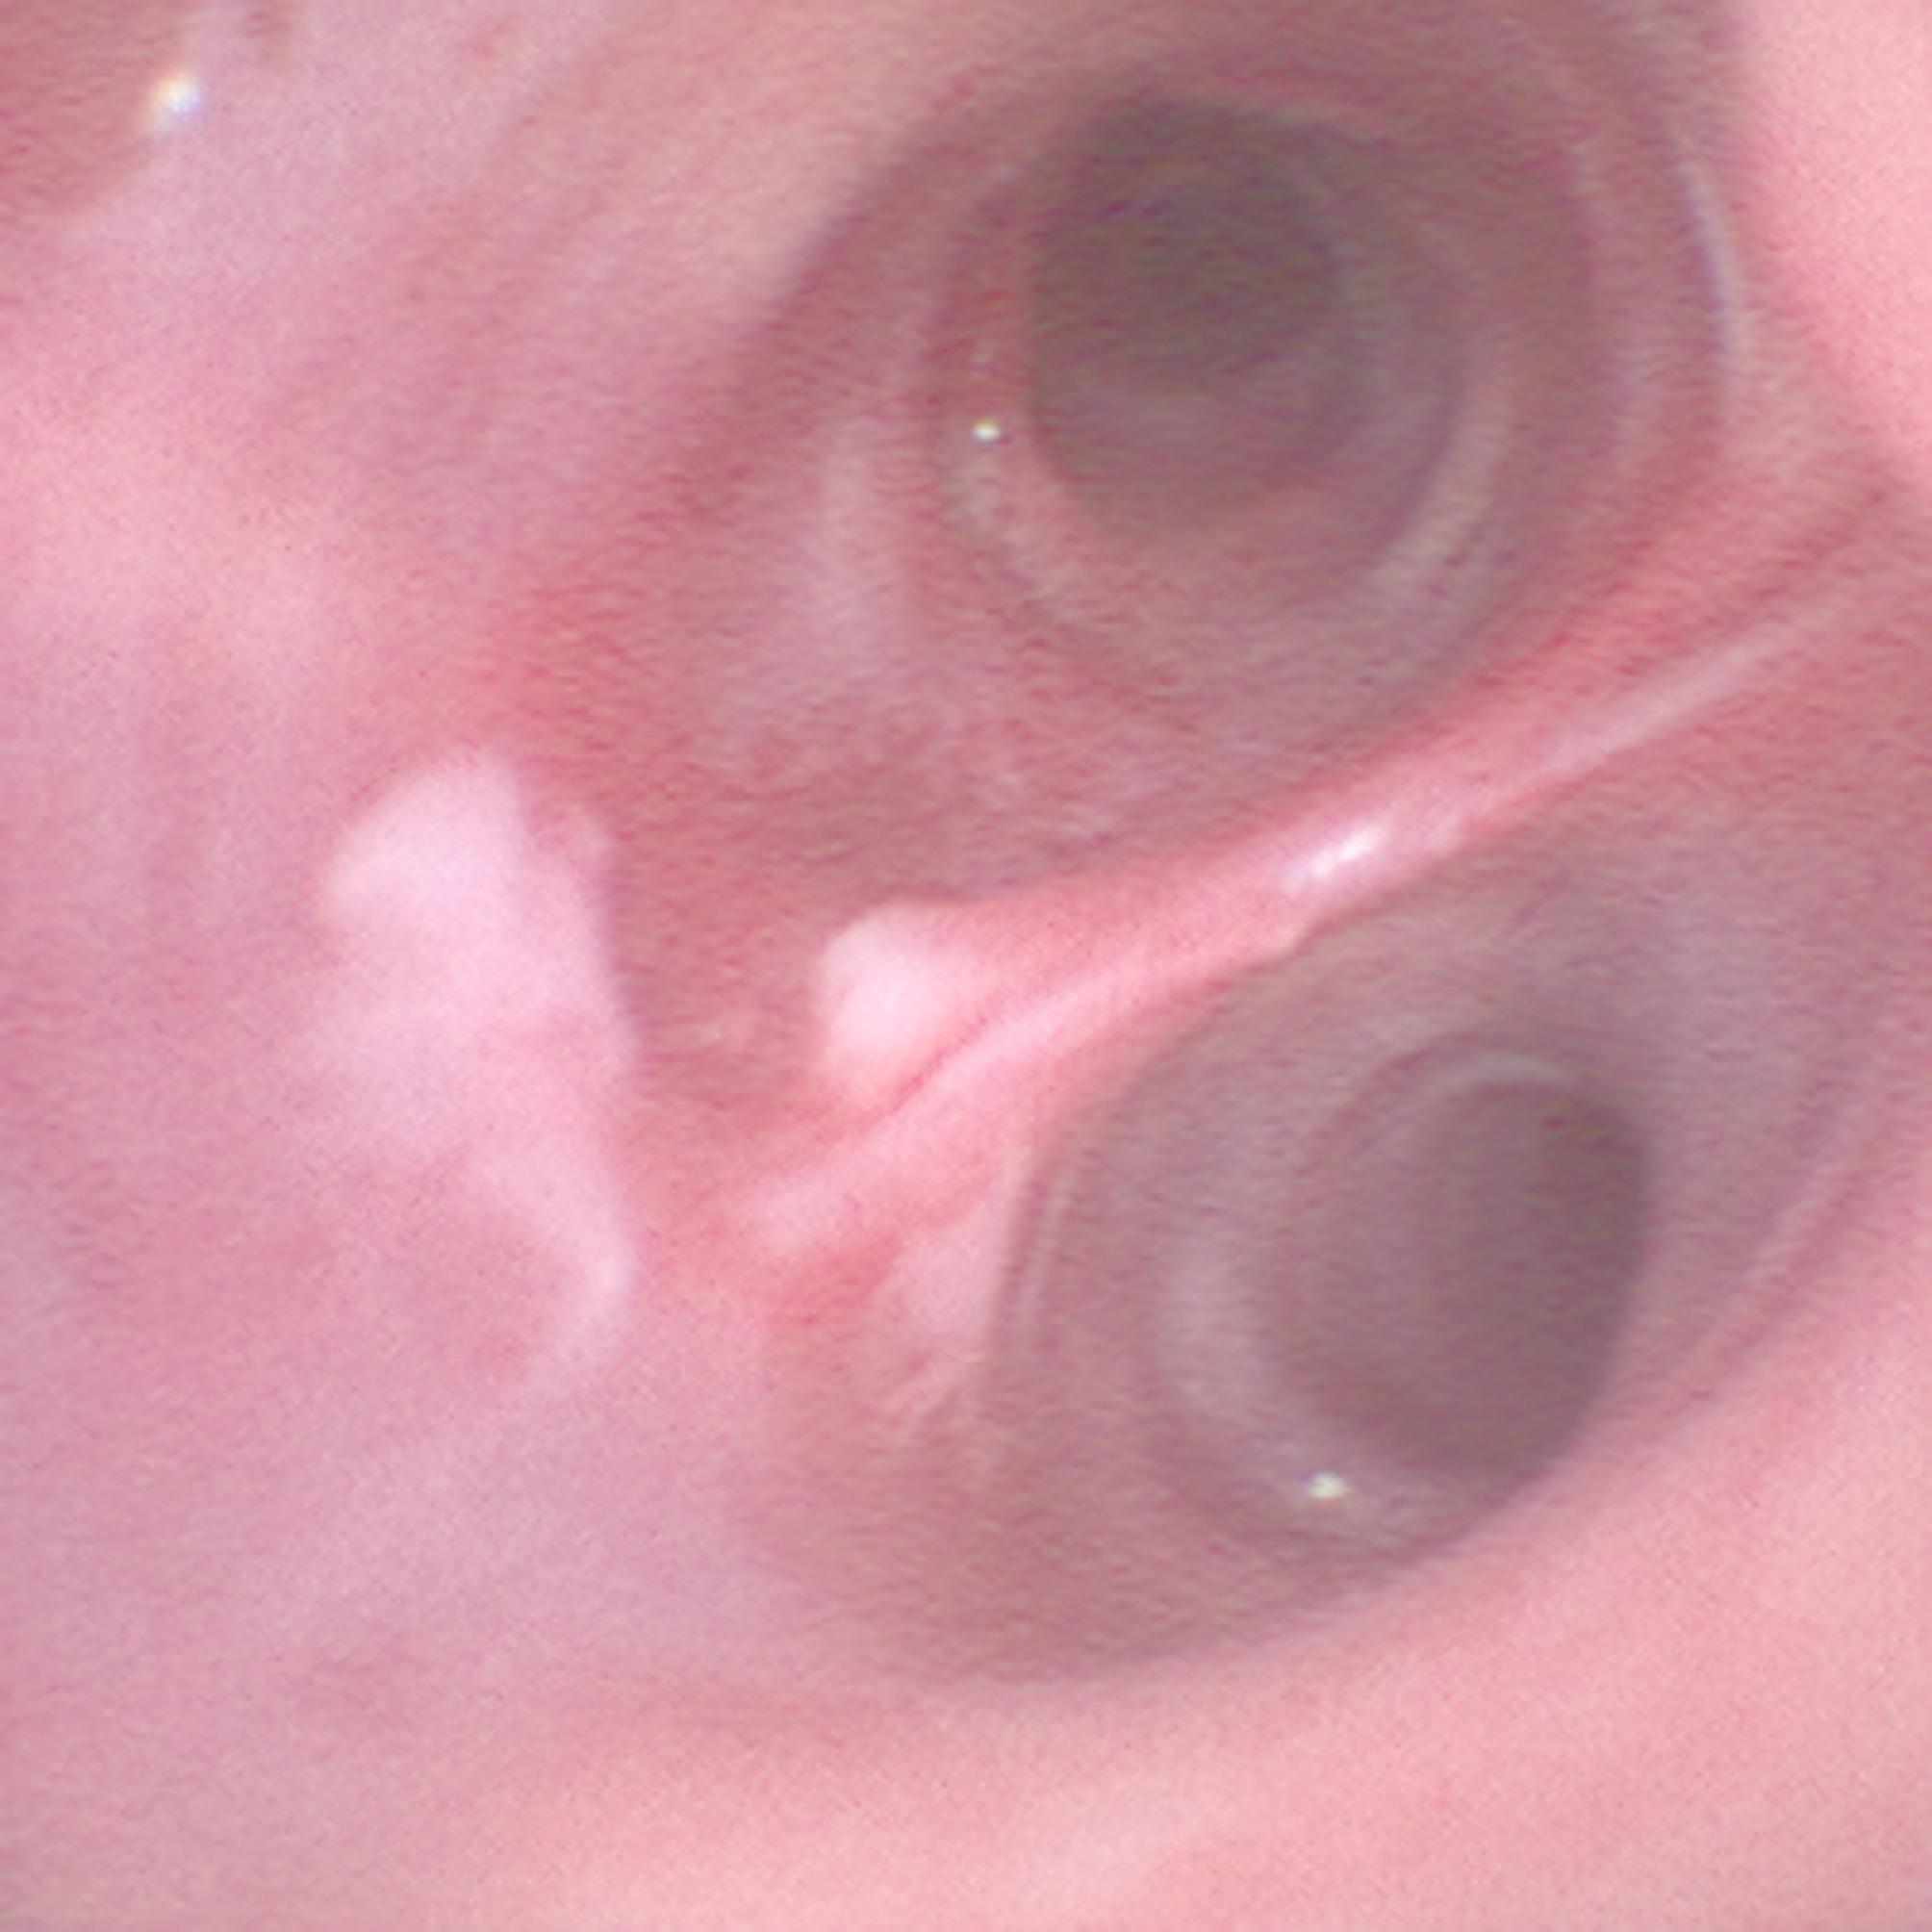

经皮扩张性气管切开术是一种成熟的技术,用于保护危重病人的气道。最常见的并发症之一是切口周围出血或解剖上邻近的大血管损伤后出血。我们报告一个病例,其中血小板减少的病人经历了危及生命的出血过程中,在分节支气管9和10,显然是由一个未识别的导丝诱导粘膜病变引起的。需要立即进行广泛的支气管镜检查和止血干预以确保氧合。为了更好地说明这种并发症,随后使用3D打印机创建了患者支气管系统的患者特异性(1:1)三维模型。总之,3d打印可以帮助可视化重症监护干预期间不常见的并发症。建议将导丝推进至气管隆突处于支气管镜控制下。字数:135。

Percutaneous dilatational tracheostomy is an established technique for securing the airway in critically ill patients. One of the most common complications is bleeding around the incision or after injury to major vessels in anatomic proximity.We report a case in which a thrombocytopenic patient experienced life-threatening bleeding during the procedure at the bifurcation between segmental bronchus 9 and 10, apparently caused by an unrecognized guide wire-induced mucosal lesion. Immediate extensive bronchoscopy and hemostatic interventions were required to ensure oxygenation. To better illustrate this complication, a patient-specific (1:1) three-dimensional model of the patient's bronchial system was subsequently created using a 3D printer. In conclusion, 3d printing can help to visualize uncommon complications during intensive care interventions. It is recommended to advance the guide wire the guide wire only until the tracheal carina under bronchoscopic control.Word count: 135.